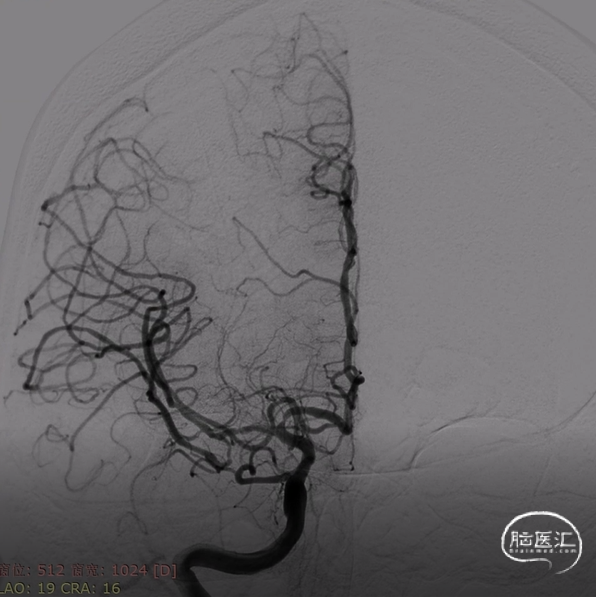

6F长鞘配合5F多功能导管,在泥鳅导丝引导下同轴技术选入右侧颈内动脉C2段,撤出导丝以及5F多功能导管,随后造影路图下将微导丝配合微导管送达右侧大脑中动脉上干M2段。6F血栓抽吸导管在微导丝配合微导管同轴引导下选入右侧大脑中动脉M1段起始,随后撤出微导丝和微导管,采用ADAPT技术持续负压抽吸,抽出一3.0mm*8.0mm暗红色血栓,再次造影提示右侧大脑中动脉复通,但可见右侧大脑中动脉M1段重度狭窄。

随后使用一次性球囊扩张导管(2.0mm*9.0mm),8个atm压力下缓慢扩张。扩张后即刻造影提示右侧大脑中动脉狭窄解除满意,前向血流eTICI3级。

观察20分钟,管腔无回缩,前向血流eTICI3级,遂结束手术。